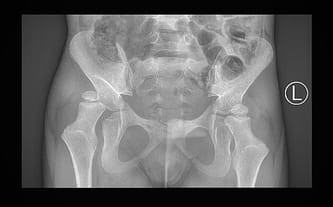

U Borysa stwierdzono prawostronne zwichnięcie stawu biodrowego, podwichnięcie lewego stawu biodrowego, obustronne spłycenie panewek stawów biodrowych i deformację koślawą bliższych stawów kości udowych. Taki stan to efekt spastyczności i jednocześnie obniżonego napięcia mięśniowego, które uniemożliwia prawidłowe funkcjonowanie układu mięśniowego i szkieletowego.